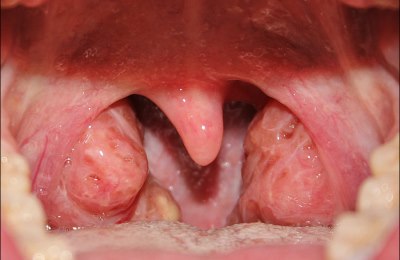

При хроническом заболевании миндалин — тонзиллите (или воспалении небных миндалин), сопровождающемся осложнениями, часто назначается оперативное вмешательство по удалению гланд.

Операции с применением лазера так же назначаются и при гипертрофии небных миндалин.

Кроме того, при гипертрофии миндалин их выступающие участки мешают нормальному дыханию и глотанию. В этом случае проводят частичное удаление гланд либо прижигание, уменьшая их в размере.

Тонзиллотомия – удаление части небных миндалин, которые выступают в дыхательные пути и мешают нормальному функционированию дыхательной системы. Операция назначается при гипертрофии небных миндалин.

При данной патологии человек сталкивается с проблемами дыхания и глотания. Увеличенные гланды так же являются причиной храпа.